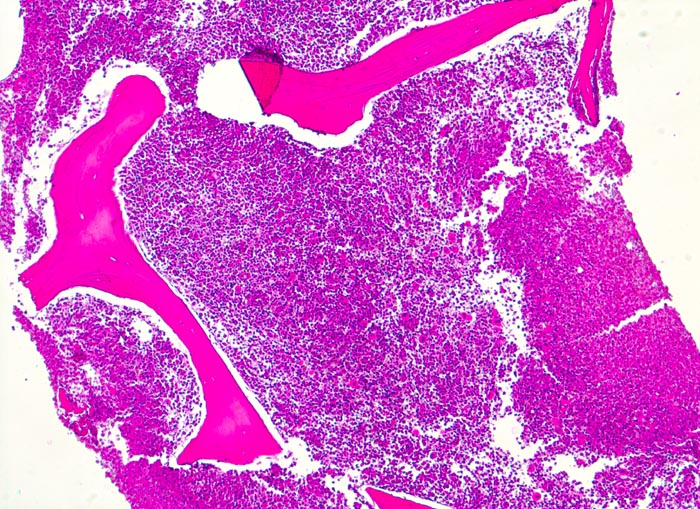

In der chronischen Phase zeigt das Knochenmark eine Hyperzellularität, welche auf eine Vermehrung der neutrophilen Granulozyten und deren Vorläufer zurückzuführen ist. Der paratrabekuläre Streifen unreifer Granulozyten kann verbreitert sein von normal 2-3 Zellschichten auf 5-10 Zellschichten. Blasten machen weniger als 5% der Knochenmarkzellen aus. Eine Blastenzahl von mehr als 10% deutet auf eine Transformation in ein akzeleriertes Stadium und von mehr als 20% entspricht einer Blastenkrise mit Transformation in eine akute Leukämie. Die Megakaryozyten sind typischerweise kleiner als normal, haben hypolobierte Kerne und sind bei 40-50% der Patienten vermehrt. Der Prozentanteil der erythroiden Vorstufen ist gewöhnlich vermindert (G:E Ratio >5:1. Die initiale Knochenmarkbiopsie zeigt bei 40% der Patienten eine Vermehrung von Reticulinfasern assoziiert mit einer erhöhten Anzahl Megakaryozyten. Das Ziel der histologischen Untersuchung des Knochenmarks besteht darin, den Anteil an Blasten im Knochenmark und damit das Stadium der Erkrankung festzulegen. Bis zu einem Blastengehalt von weniger als 10% der kernhaltigen Zellen spricht man von einer chronischen Phase, zwischen 10 und 20% von einer akzelerierten Phase und bei über 20% liegt eine akute Leukämie vor.

• Fast 100% Zellularität des blutbildenden Marks (praktisch keine Fettzellen, sogenanntes "packed marrow").

• Stark vermehrte, ausreifende Myelopoese.

• Der paratrabekuläre Saum unreifer myeloischer Zellen ist verdickt auf 5 bis 6 Zellen.

• Verdrängung der Erythropoese.

• In Gruppen liegende vermehrte nacktkernige (= kein Zytoplasma) verkleinerte Mikromegakaryozyten mit hypolobierten Kernen.